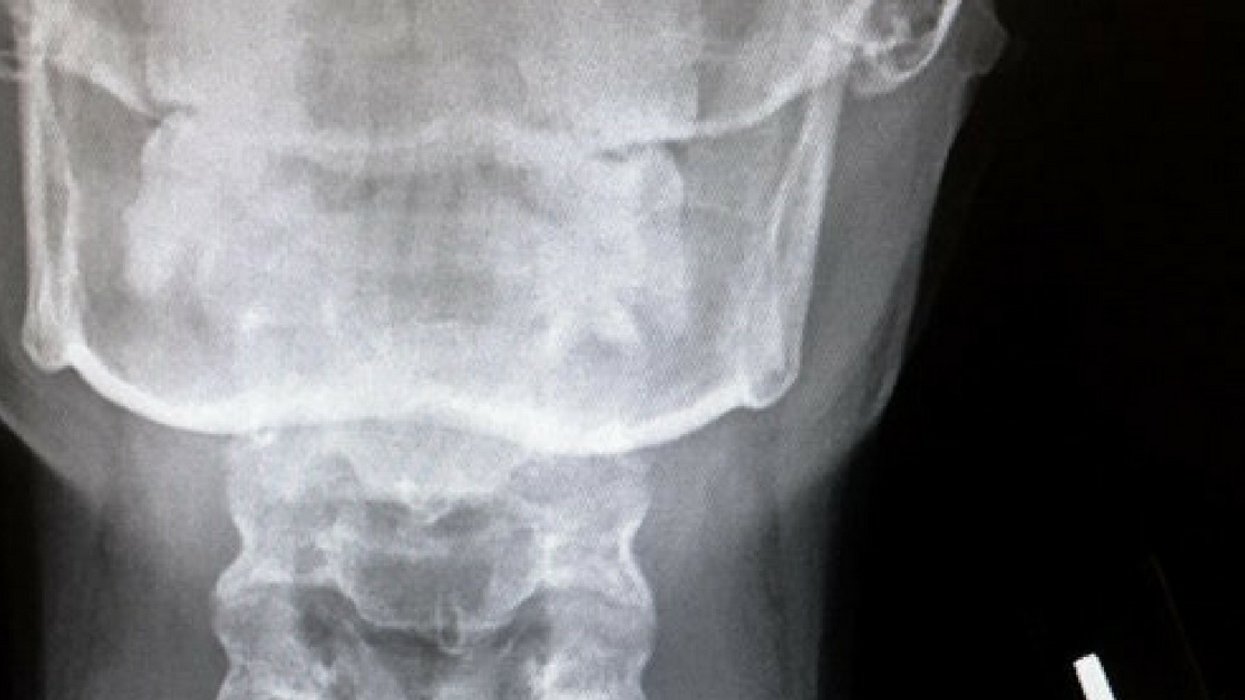

Here's that radiograph of her throat, complete with Batman bling:

Bat earring found it's way into my inhaler.

14 hours in the ER and one surgery later, I am now known as bat girl.